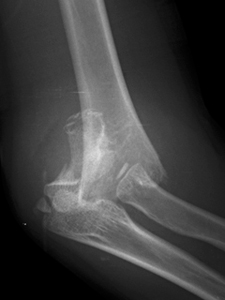

また、レントゲンで側面から撮影を行うと、尺骨が後方に抜けてしまっているのがわかります。下のレントゲン画像では、尺骨が後方に飛び出して抜けていることが一目瞭然です。

治療は、受傷からほとんど時間が経っていないときは、麻酔なしでも徒手整復できます。ただ、そのときに患部周辺の組織が損傷することを防ぐために、麻酔下での徒手整復を行うこともあります。